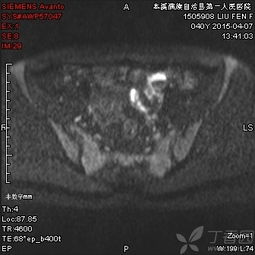

6、盆腔內(nèi)病變:包括膀胱、前列腺、子宮、卵巢、直腸良、惡性占位病變,特別是前列腺增生,子宮內(nèi)膜異位癥等。MRI多方位、大視野成像可清晰地顯示盆腔的解剖結(jié)構(gòu)。尤其對女性盆腔疾病具有重要診斷價值,對盆腔內(nèi)血管及淋巴結(jié)的鑒別較容易,是盆腔腫瘤、炎癥、子宮內(nèi)膜異位癥、轉(zhuǎn)移癌等病變的最佳影像學(xué)檢查手段。